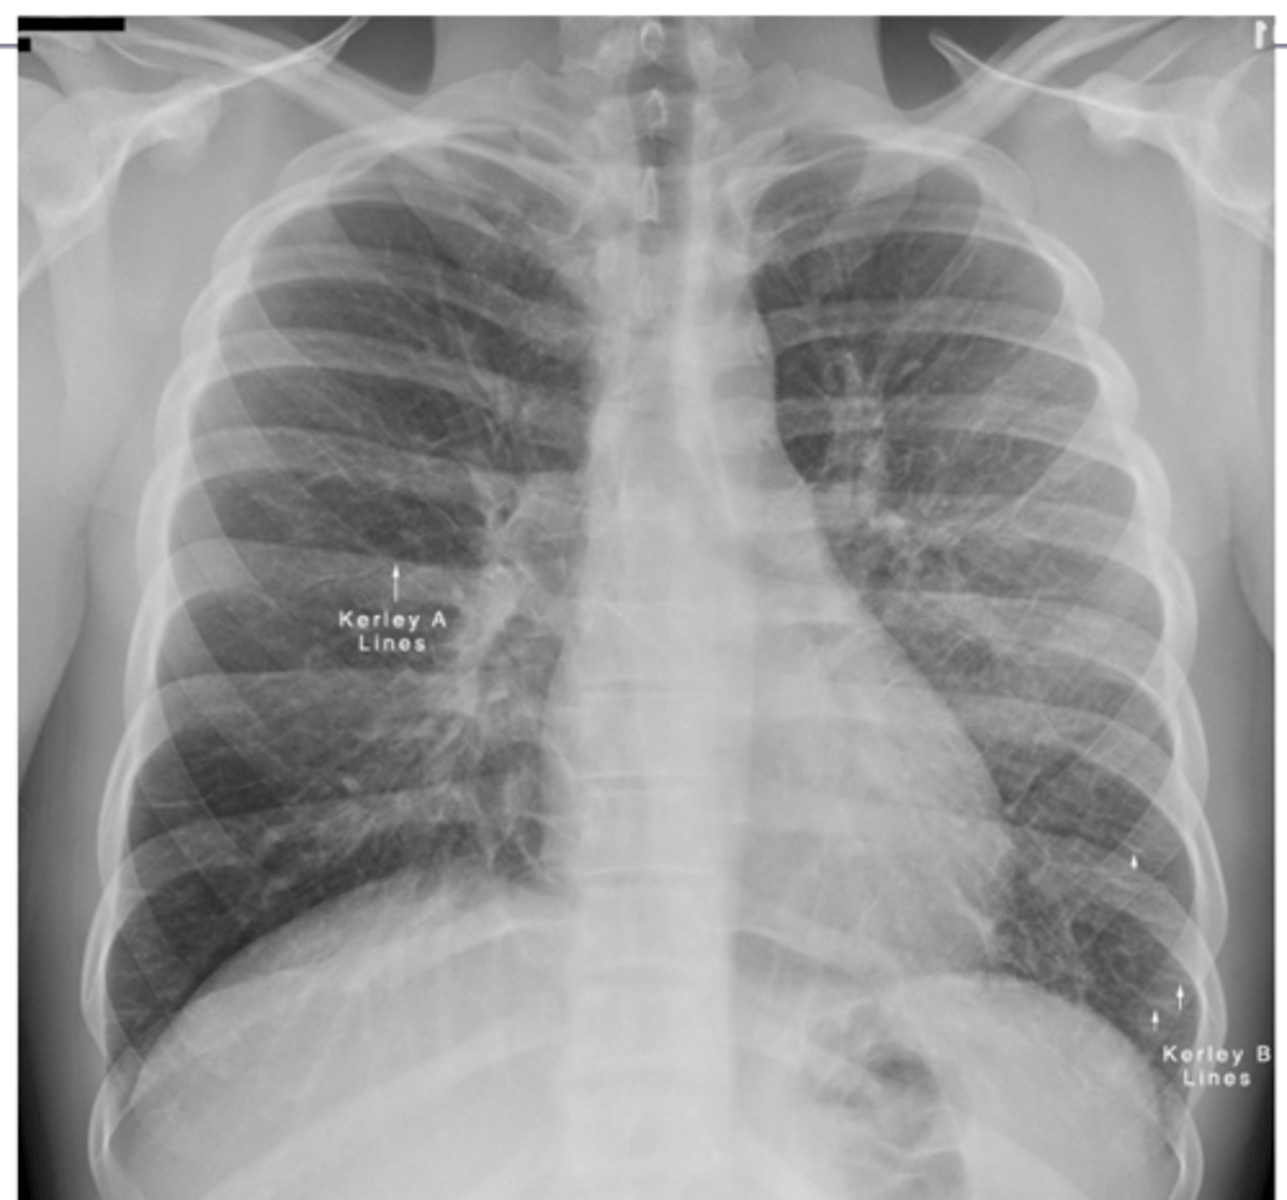

What are kerley A and B lines?

•Kerley A lines are linear opacities extending from the periphery to the hila caused by distention between peripheral and central lymphatics

•Kerley B lines are small, horizontal, peripheral straight lines demonstrated at the lung bases that represent thickened interlobular septa on CXR.

<p>•Kerley A lines are linear opacities extending from the periphery to the hila caused by distention between peripheral and central lymphatics</p><p>•Kerley B lines are small, horizontal, peripheral straight lines demonstrated at the lung bases that represent thickened interlobular septa on CXR.</p>

What are linear interstitial infiltrates also called? What is this sign commonly associated with?

Kerley lines --> interstitial pulm edema

<p>Kerley lines --&gt; interstitial pulm edema</p>